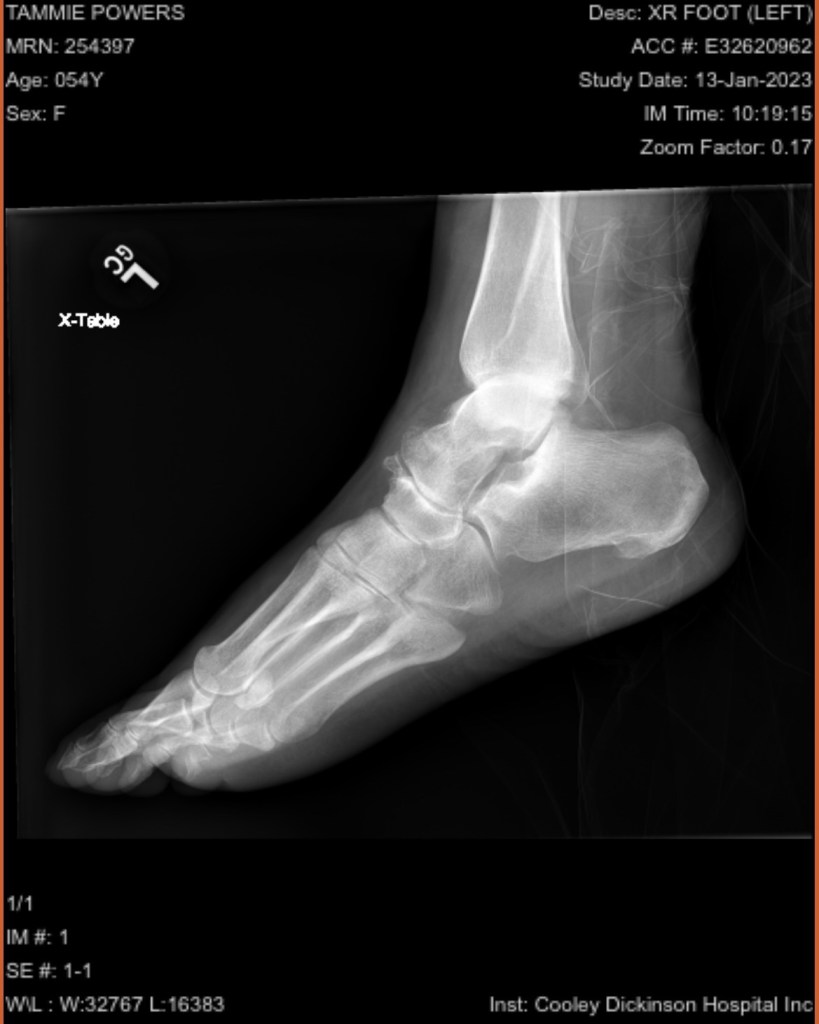

Once I got there they stuck me in a room, and finally did some x-rays. After some prodding they gave me some pain meds, and a diagnosis. A bimalleolar fracture with ligament and tendon damage.

Then came the fun part, a shot of lidocaine in the joint, and 2 doctors reducing the fracture to get it close to the way it was. I went home with pain meds , crutches and instructions to go to Cooley ortho walk in on Monday.

Walk in ortho clinic gave me the results that I expected, but didn’t want. It would be a surgical repair. On January 23, I was at the Kittredge Surgical Center at 6:00 am. My ankle was pinned, plated, the talus was relocated and the ligaments and tendons were repaired. It is likely that the incision went right through my tattoo. So eventually that will need to be repaired as well. I will be non weight bearing for 8-12 weeks, my knee scooter has become my best friend. Because crutches and I don’t get along.